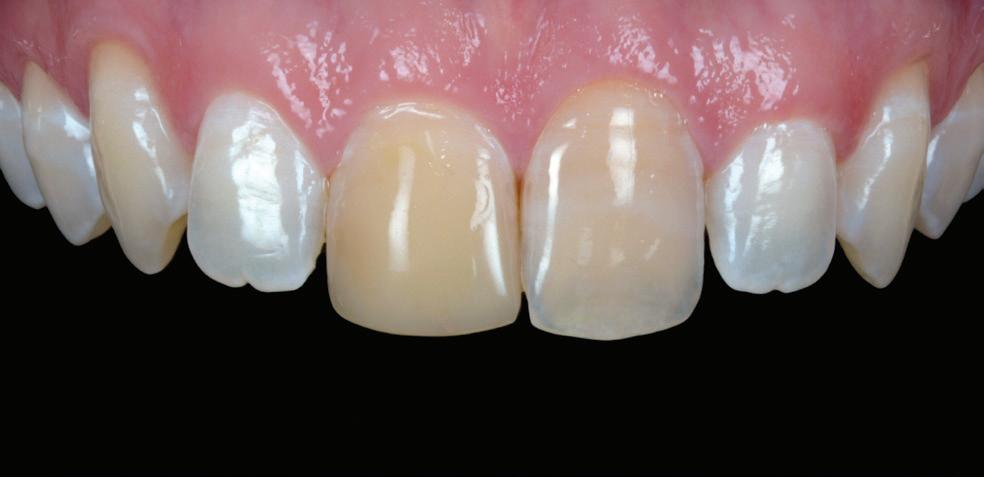

January/February 2024 Australasian Dental Practice 7 | VOLUME 35 | NUMBER 1 JANUARY/FEBRUARY 2024 194 Smart autoclave for fast, dependable sterilisation 198 A-dec sets standard in infection control 100 Designing an efficient sterilisation room: A guide 104 Preventing needle stick injury surgery design 140 Art deco style at Spa Dental 140 84 100 READ ME FOR CPD READ ME FOR CPD clinical excellence 110 Taking on the challenge with attention to detail 120 Block selection for monolithic CAD/CAM restorations - Part 2 126 Pigeon pair: Shining 3D Wireless IOS and MetiSmile Facial Scanner 134 Biodentine™ in the treatment of Molar Incisor Hypomineralisation (MIH) in paediatric dentistry: A case report READ ME FOR CPD 126